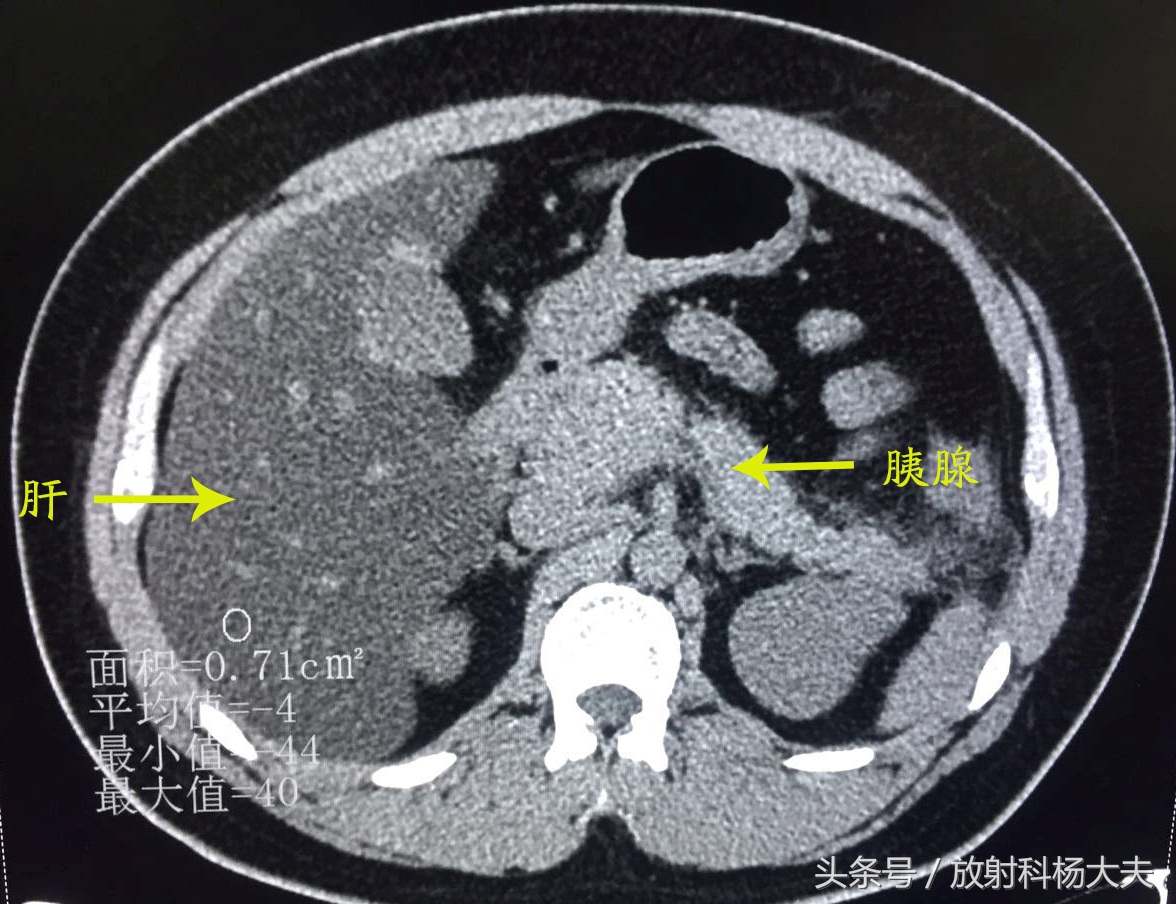

放射科的急诊总是会遇见各种急患,外伤的、头晕头痛的、恶心呕吐的、腹痛难耐的...前几天夜班来了一位身材略胖的小伙子,29岁,由于跟朋友进食火锅后突发上腹疼痛就诊,左上腹为著,为持续性胀痛,疼痛不可耐受,并向后背部放射,无肩部放射痛,疼痛不因体位变化而缓解,伴寒战、发热、大汗。做了CT,其图像如下所示:

可发现肝脏密度明显弥漫性减低,且明显低于同层面脾脏密度。胰腺周围可见渗出改变。腹痛原因找到了----急性胰腺炎伴重度脂肪肝,可这肝脏密度也太低了。